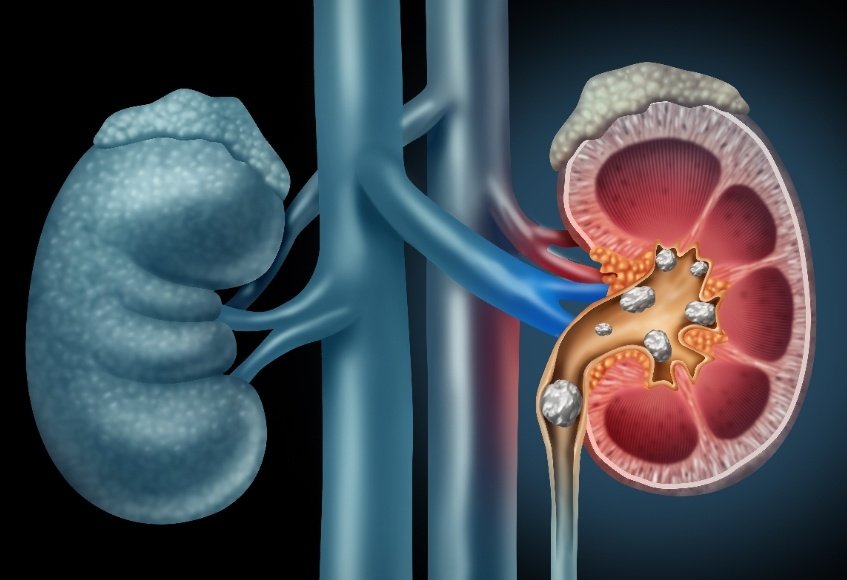

📌اليوم بتكلم عن حصوات الكلى والمسالك البولية ..

⛔اسباب تكوين الحصوات وليه أحنا من اكثر الدول الي تعاني من الحصوات.

⛔مضاعفات ترك الحصوات وعدم علاجها.

⛔اسباب تكوين الحصوات وليه أحنا من اكثر الدول الي تعاني من الحصوات.

⛔مضاعفات ترك الحصوات وعدم علاجها.